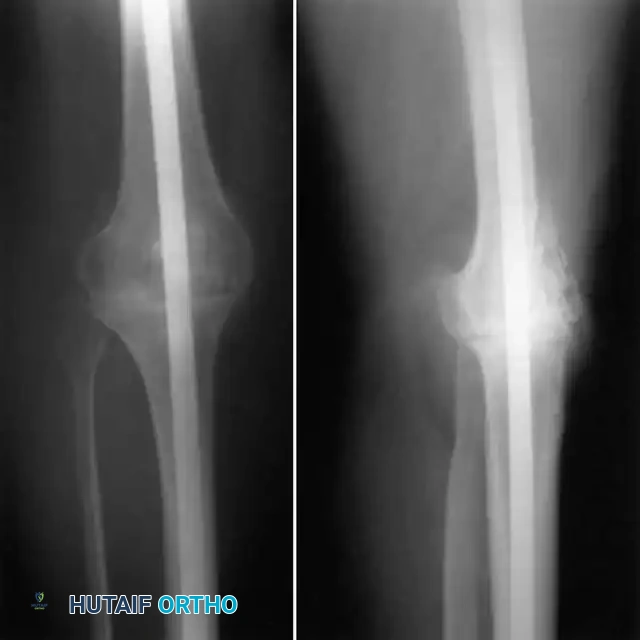

Periprosthetic fractures, particularly supracondylar femur fractures, are increasing in incidence due to an aging population and the rising number of TKAs performed. Risk factors include advanced age, osteoporosis, chronic steroid use, and anterior femoral notching during the index arthroplasty.

Radiographs demonstrating a periprosthetic supracondylar femur fracture managed with a lateral locking plate.

Classification and Management:

The Lewis and Rorabeck classification is widely used for supracondylar fractures:

* Type I: Undisplaced fracture, prosthesis intact. Managed non-operatively with a cast or brace.

* Type II: Displaced fracture, prosthesis intact. Managed with open reduction and internal fixation (ORIF) using lateral locking plates or retrograde intramedullary nails.

* Type III: Fracture with a loose prosthesis. Requires revision arthroplasty using a long-stemmed femoral component, often with distal femoral replacement (megaprosthesis) if bone loss is severe.